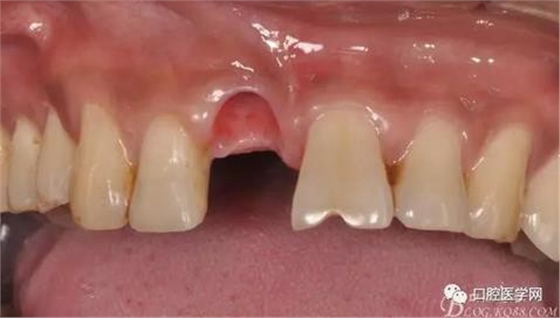

圖4 術前正位頜面照

圖5 拔除殘根

圖9 三個月后袖口形成正位照